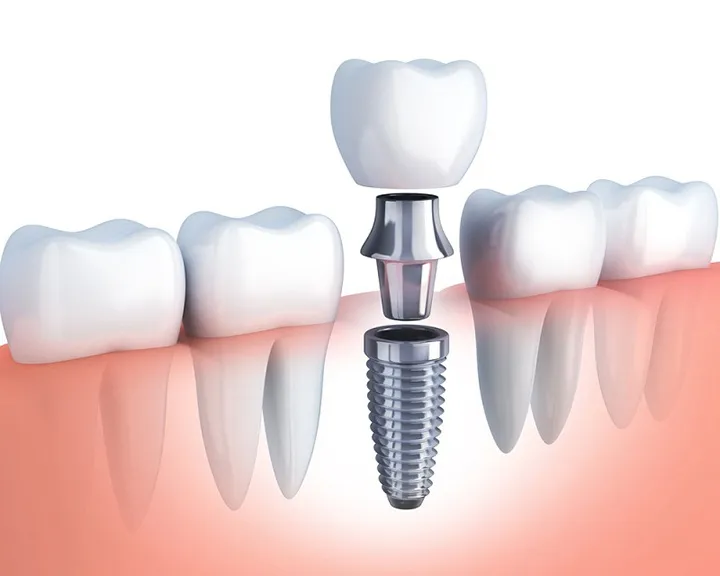

Cấy ghép Implant phức tạp là những ca điều trị phục hồi răng mất, trong đó có sự hiện diện của một hoặc nhiều yếu tố rủi ro và khó khăn về mặt giải phẫu, xương hoặc mô mềm, buộc phải áp dụng các kỹ thuật phẫu thuật phụ trợ đặc biệt để tạo điều kiện tối ưu cho sự tích hợp xương của trụ Implant.

Cấy ghép Trụ Implant (Giai đoạn 2): Khi nền xương đã được tái tạo thành công, trụ Implant sẽ được đặt vào vị trí đã được lập kế hoạch 3D. Với công nghệ cấy ghép số hóa tại Dr. Green, quá trình này được thực hiện nhanh chóng, chính xác và ít xâm lấn hơn.

Phục hình Răng sứ (Giai đoạn 4): Sau khi Implant tích hợp xương hoàn toàn, bác sĩ sẽ tiến hành lấy dấu và chế tạo mão sứ cố định, hoàn tất quá trình phục hình.